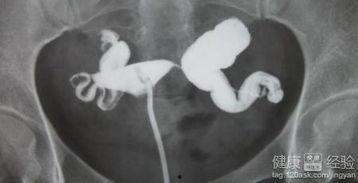

接下来,让我们来看看这个手术是怎么进行的。这里,我找到了一些专业的手术视频,可以让你更直观地了解整个过程。

为了让你更直观地了解手术过程,我找到了一些输卵管积水手术的视频。这些视频都是真实案例,你可以看到医生是如何操作的。

1. 手术开始:医生首先将腹腔镜插入你的腹部,然后通过摄像头观察输卵管的情况。

2. 找到积水部位:医生会仔细寻找积水的地方,并用工具将其清除。